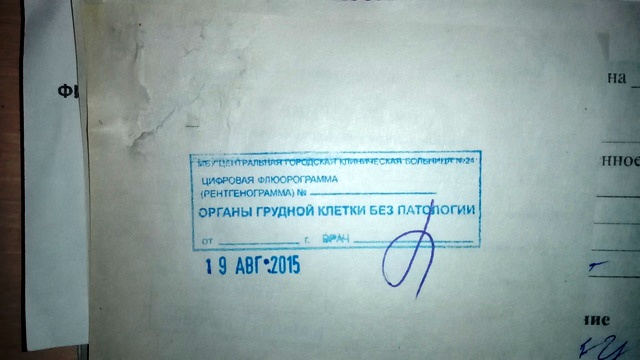

Фотографии рентгеновских снимков без необходимости направления от врача